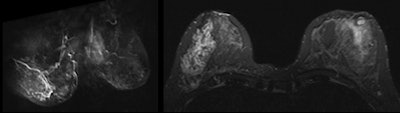

Patient presented with spontaneous, brown, right nipple discharge that had lasted for one year. Personal history, physical examination, mammography and ultrasound (images above) revealed only benign findings (bilateral fibroadenomas and duct ectasia in the outer quadrants of the right breast). During cytological analysis of secretion material, a papillary lesion without atypia was found. All images courtesy of Dr. Michele Lorenzon.Based on these results and on published papers, in cases of suspicious nipple discharge with inconclusive conventional imaging, Lorenzon and his colleagues now perform breast MRI instead of galactography. However, they are collecting additional cases of patients with suspicious nipple discharge undergoing breast MRI.

Breast MRI showed a suspicious non-mass-like enhancement in the inferior-outer quadrant of the right breast, occupying approximately 50 mm in the axial plane. The final pathological diagnosis was papillary carcinoma with extensive intraductal carcinoma.